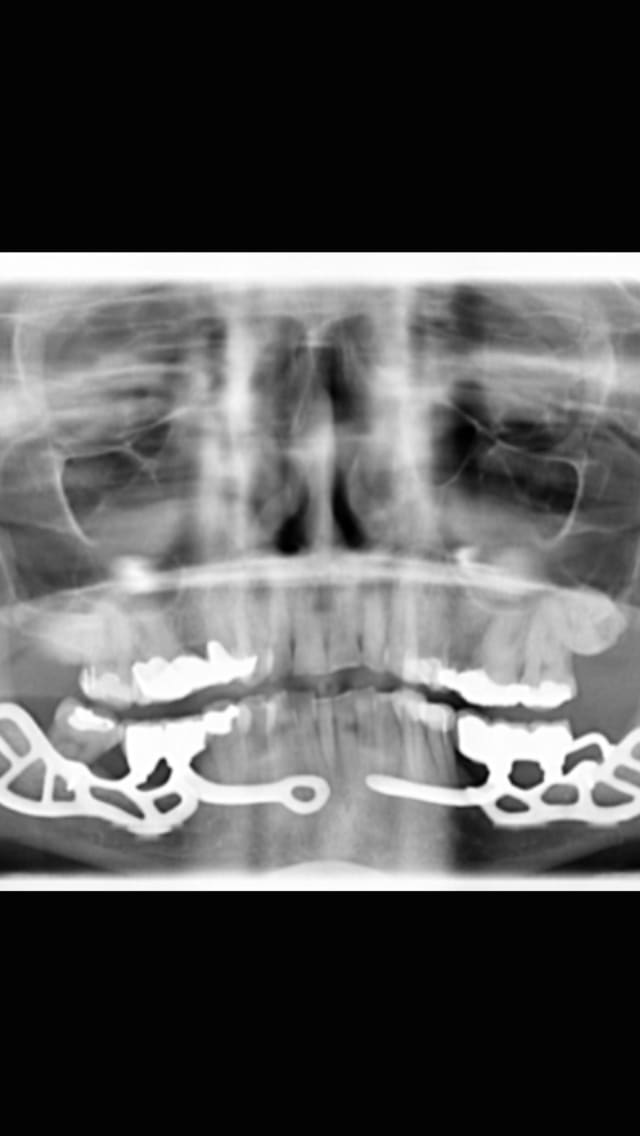

De la pano la moins marrante Ă  la plus marrante :

Regarde moi ça 4 Implants et on va jusqu'aux 7 voir jusqu'aux 8 sans problùme 😊